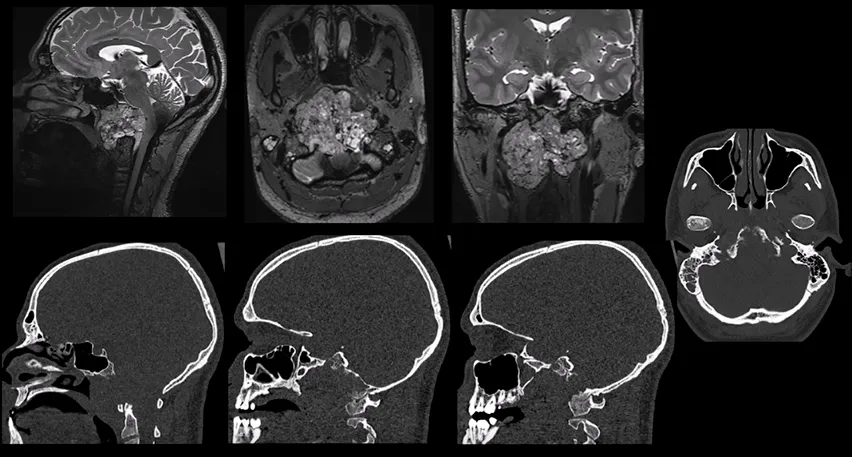

患者路易的主要临床症状表现为颈部疼痛、严重的吞咽障碍以及双侧舌下神经麻痹(右侧为完全性麻痹伴舌肌萎缩,左侧为部分性麻痹)。为直观了解路易颅内肿瘤的实际大小,可参考下方影像图片。

影像学检查确实显示,路易颅内的肿瘤已对连接颅骨与颈椎的骨性结构造成了严重的破坏性改变。在手术切除肿瘤之后,该区域的骨骼稳定性将难以维持。可以做一个形象的比喻:颅颈交界区如同连接“头部”(颅骨)与“躯干”(脊柱)的精密榫卯结构。肿瘤破坏了这个结构。外科医生在手术中不得不移除这个已被破坏的“榫卯”,但在取出肿瘤后,必须立即使用“钢板与螺钉”(即内固定系统)将这个连接部位重新进行牢固的固定与加固,否则头部的稳定性将无法保障。

图A和图B:术前CT扫描显示颅颈交界区脊索瘤,侵犯斜坡-枕骨髁并呈溶骨性破坏。

图C:术前磁共振成像(MRI)显示肿瘤巨大,并向硬膜内脑实质浸润性生长。

脊索瘤是一种起源于脊索细胞残余的罕见中线肿瘤。在成人患者中,最常见发病部位为骶骨区域(约占50%),其次为颅底及颅颈交界区(约占30%)和活动性脊柱节段(约占20%)。诊断时的平均年龄约为55岁,而颅底脊索瘤通常累及相对年轻的人群。肿瘤全切除联合质子束放射治疗被推荐为理想的治疗策略。

由于病灶具有侵袭性且位置深在,实现肿瘤全切除常常伴随显著的手术风险。尤其需要指出的是,根据文献报道,颅颈交界区脊索瘤的预后通常较颅底脊索瘤更差。此类肿瘤倾向于侵袭斜坡、岩骨、枕骨髁、C0-C1及C1-C2关节、上颈椎,导致骨质破坏和颅颈交界区不稳。它们也常向椎前间隙和咽旁间隙的软组织延伸,使得完整切除更加困难。椎动脉受累亦是常见表现。